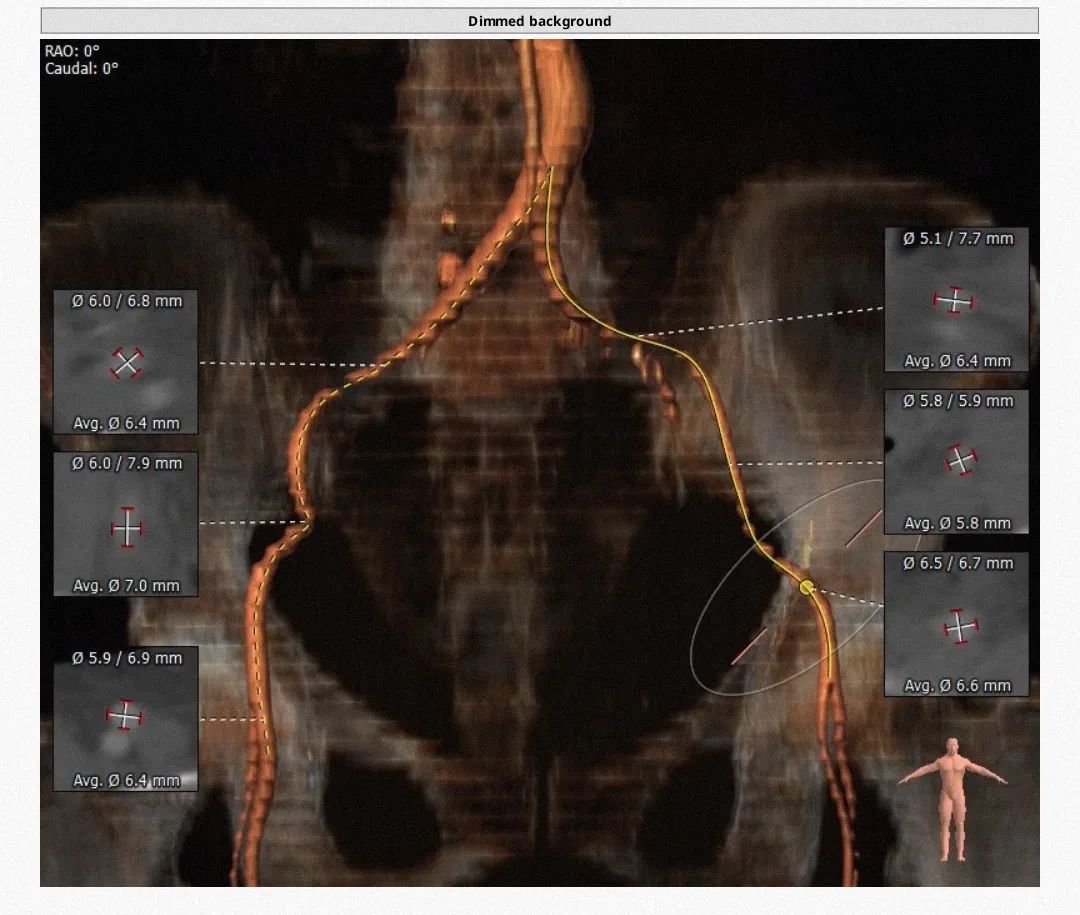

类TYPE2型二叶瓣,极重度钙化,左冠高度稍低,右冠高度可,升主动脉增宽,最宽处约40mm,心脏角度不大,左室大,心尖部局部心肌薄弱作。

1.瓣膜选择:瓣环径24mm,但属于type2型二叶瓣,钙化范围广、程度重,球囊选择18,根据预扩结果进一步明确瓣膜型号,备L23/26/29。

2.冠脉风险:瓣叶较长,右冠高度尚可,左冠9.3mm偏低,但由于钙化分布广且重,瓣叶可能不会被推挤到冠脉开口,术中根据球扩进一步明确。

3.释放:钙化重,使用A+,可考虑高位释放,采用慢快慢节奏。

4.通路:心脏角度不大,主动脉弓平滑无夹角,外周动脉直径超过6mm,无太大风险。